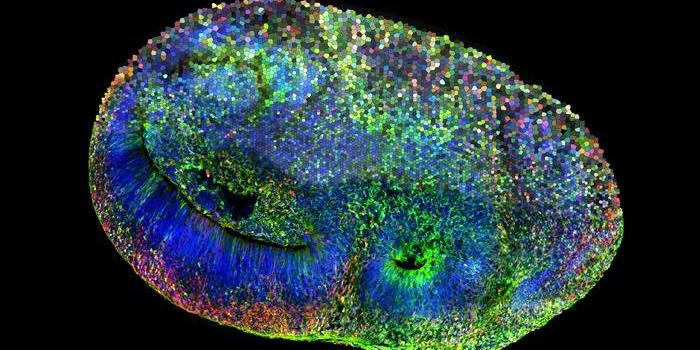

AUG 29, 2024Cell & Molecular BiologyScientists have used an organoid model to gain new insights into Huntington's disease, a fatal genetic disorder that cau ...